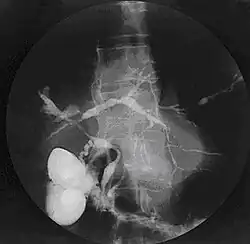

Primær skleroserende kolangitis er en autoimmun, kronisk betændelsestilstand i galdegangene. Sygdommen risikerer at lukke galdegangene, hvorved der ophobes galdestoffer i blodet og galdeafløbet forhindres.[1]

Sygdommen ses ofte hos personer, der lider af Colitis ulcerosa (ofte) og Crohns sygdom (sjældnere).[1]

Symptomer på primær skleroserende kolangitis kan være træthed, hudkløe og gulsot. Der er også større risiko for akutte infektioner og galdestensanfald.[1]